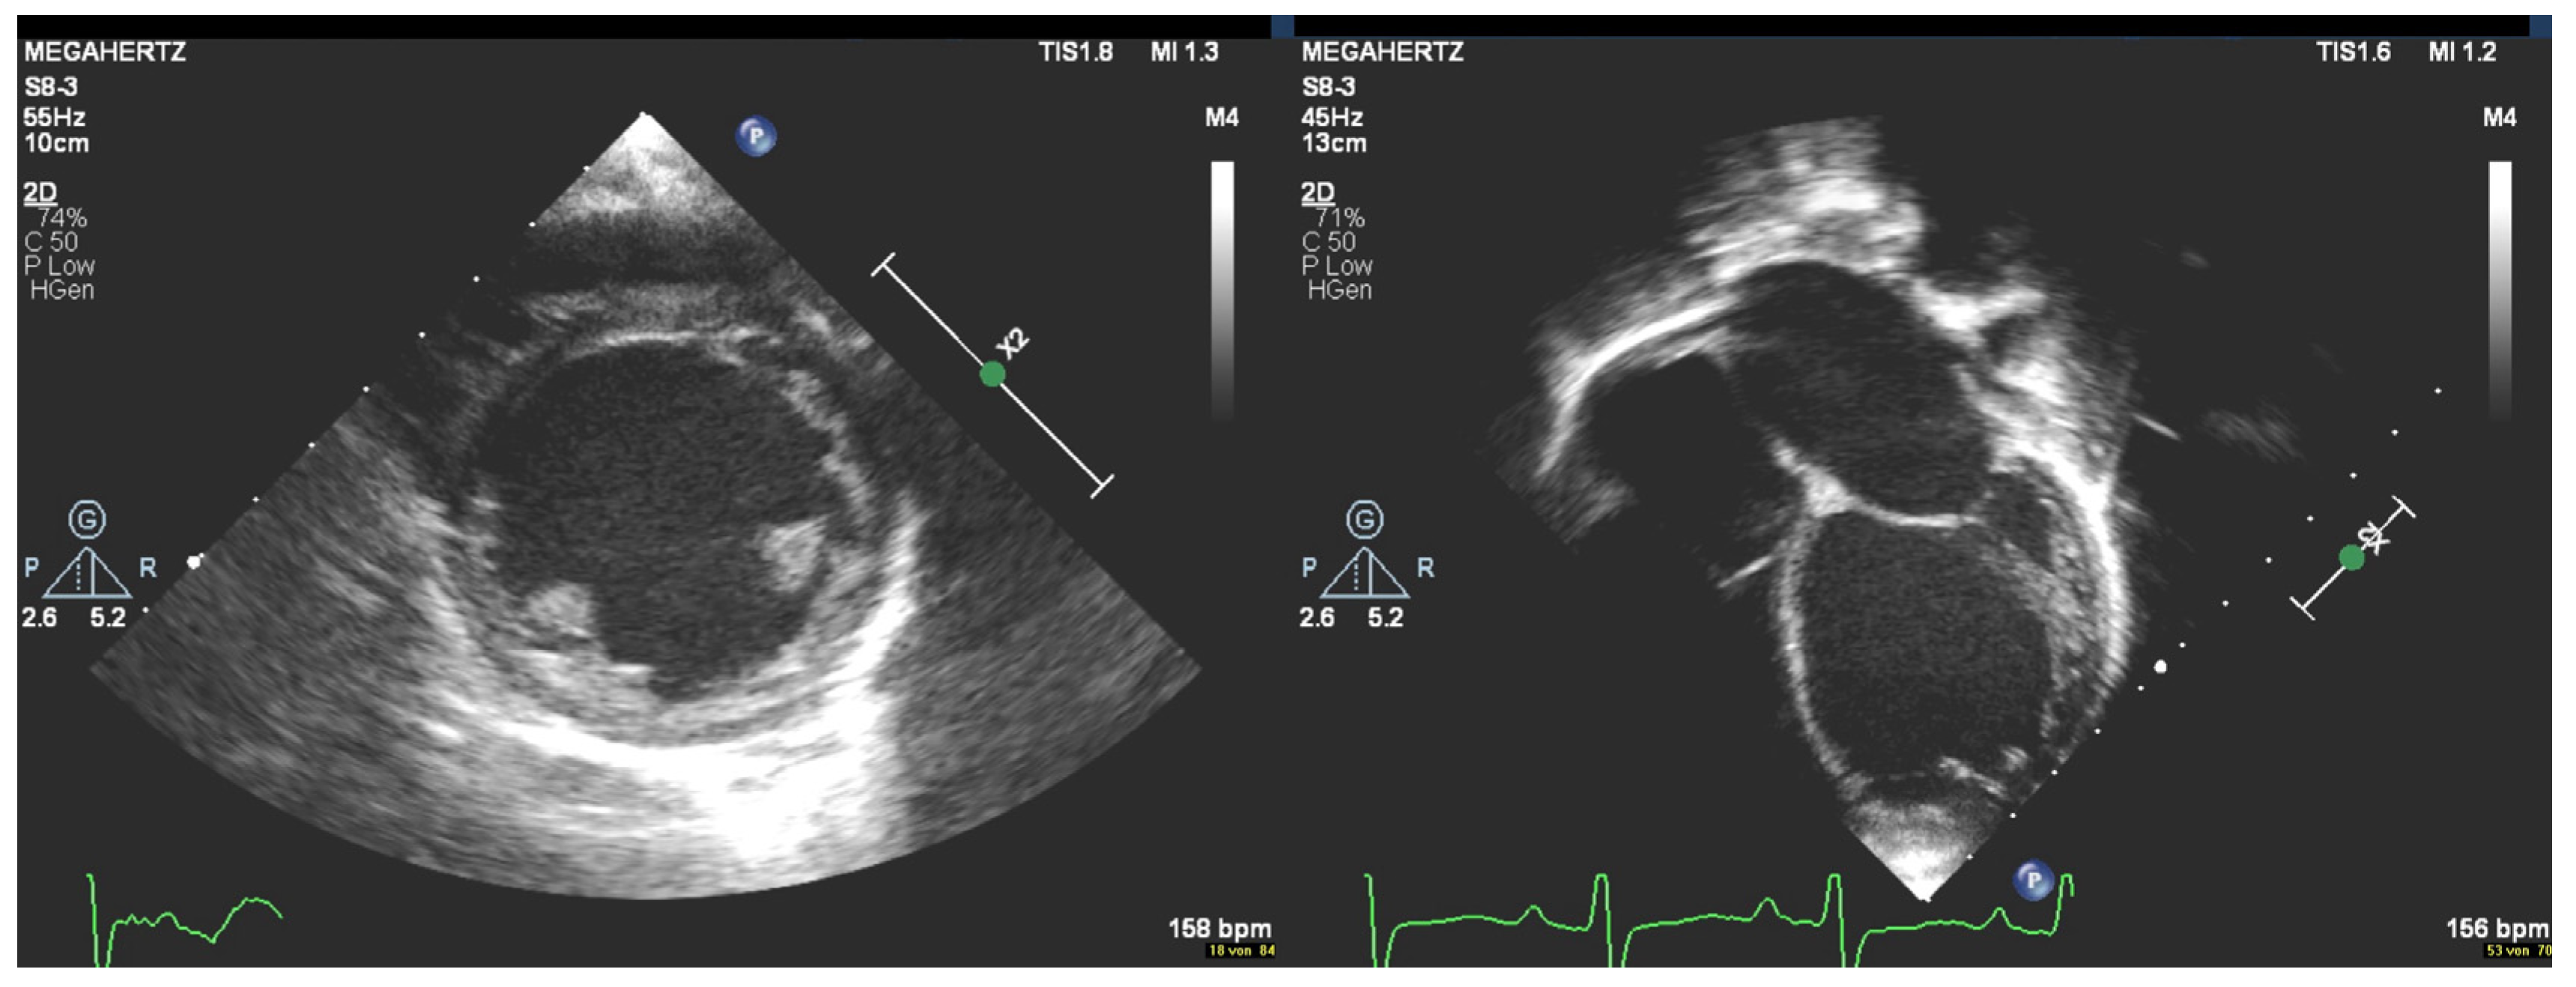

2. Case Description